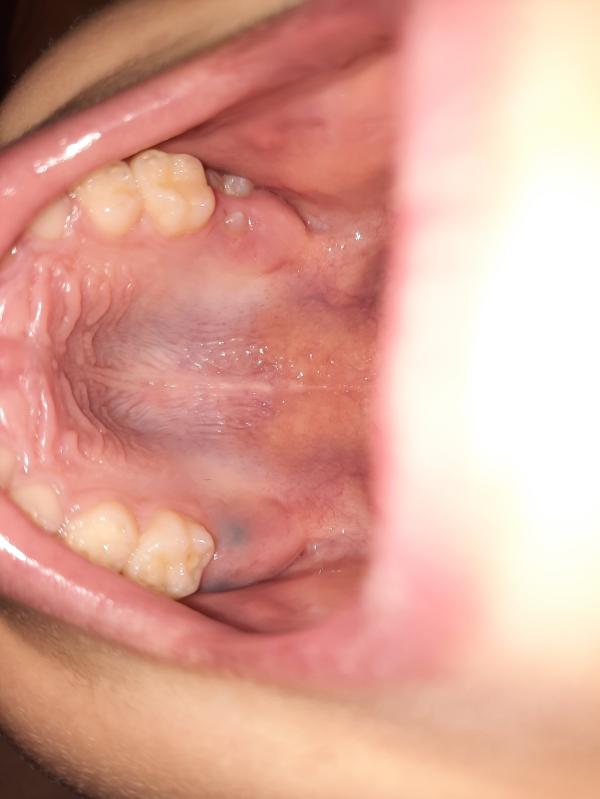

Девочки!!! Сейчас смотрела ротик у мальчишек, и у одного обнаружила черные пятна там, где должен прорезываться постоянный коренной. Кто-то сталкивался? К стоматологу бежать или сам прорежется?

Не надо никуда бежать. Всё нормально на фото, зубик давит на десну и образуется гематомка, вскоре он её совсем прорвёт и вылезет.

Ну вообще, это гематома(

Зуб прорастает и прорывает слизистую. Если нестерпимо болит, то можно к стоматологу, он вскроет под анестезией. У малышей также режутся.

Это гематома прорезывания.